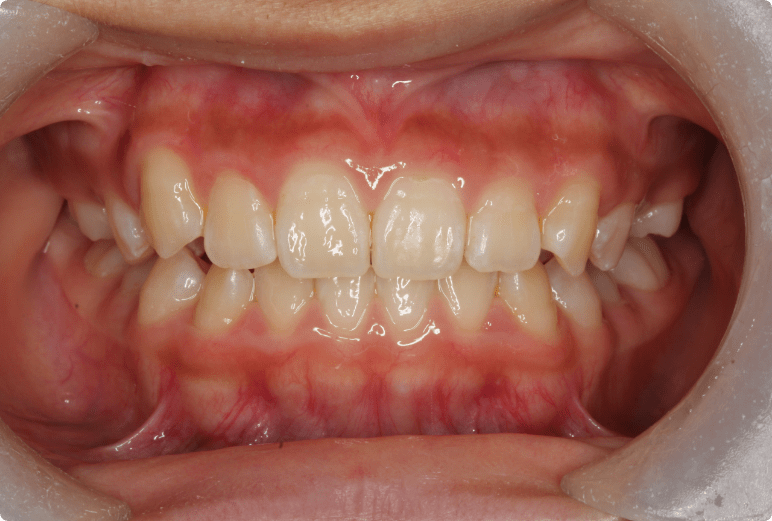

八重歯を改善した症例

BEFORE

AFTER

症例概要

年代、性別

12歳 女の子(成人と同様の矯正治療)

主訴

八重歯

診断

骨格性Ⅰ級、歯性Ⅱ級、前歯部叢生

治療内容

上顎左右4番抜歯、唇側ワイヤー矯正、リテーナー

治療期間

2年+メンテナンス

治療リスク

痛み、歯根吸収、歯肉退縮

治療費用

990,000円(税込)